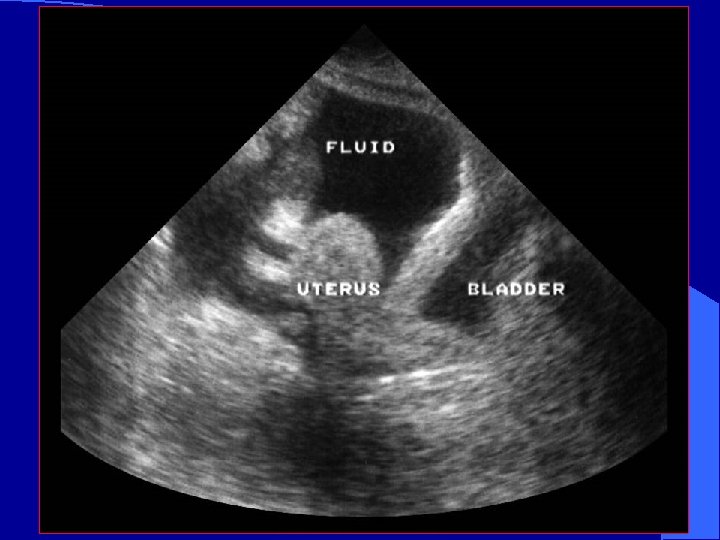

Pelvic View Probe should be placed in the suprapubic position l Either can be transverse or longitudinal l Helpful to image before placement of a Foley catheter l

Normal Transverse pelvic Fluid in pelvis

Pelvic View – Sagittal clot Fluid in front of the bladder l If bladder is empty or Foley already placed: Trick of trade l – IV bag on abdomen – Scan through bag bladder

Blood in the Pelvis

Free fluid in the pelvis